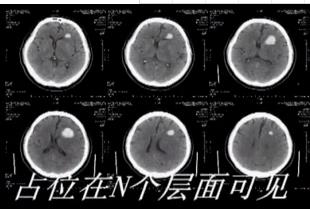

19.试述脑内血肿不同时期 CT 表现

答:CT 表现(血肿分为三期):

急性期

≤1 周,圆形或肾形,均匀高密度,周围伴有水肿,增强无强化。

吸收期

2 周~2 个月,血肿中央高密度,边缘模糊,占位效应明显,周围水肿由重到轻。增强可

有薄环状强化。

囊腔期

≥2 个月,低密度囊腔,水样密度,无水肿与占位效应。增强无强化。